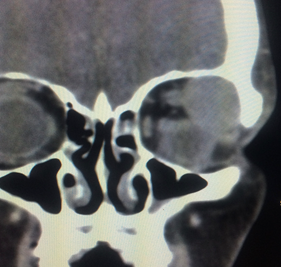

Our eyeball and its content are bounded within a bony socket which is made up of several orbital bones. The content of the eye socket is mainly the globe, extraocular muscles, blood vessels, nerves, and fat. There are many disease entities that may arise from within this confined space. For example, orbital tumours, orbital inflammation & infection, orbital fractures,

Orbital cellulitis is an orbital infection of the soft tissues within the eye socket. It is most often due to an extension of infection from nearby sinuses. It can also be caused by direct infection following local injury such as insect bite and penetrating eyelid injuries. Spread of infection from the face or teeth via blood can also be the cause. Patients may present with blurred vision, double vision, eye pain, bulging eye, eyelid swelling and redness. Fever may accompany the other symptoms. Diagnosis is based on history, clinical examination and imaging such as CT scan or MRI. First line of treatment is systemic antibiotics and sometimes surgical drainage may be required.